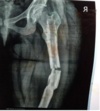

Q9-The above picture show: a- Non closure of epiphyseal line between the lower end of humerous, upper end of radius and ulna with their shafts, b- Closure of epiphyseal line between the lower end of femur with the shaft. c- Non closure of epiphyseal line between lower femur with shaft. d- Closure of epiphyseal line between lower end of humerous with shaft.

b- Closure of epiphyseal line between the lower end of femur with the shaft.

229

Ql0 -The estimated age is: a- Above 23 yr. b-Above 21 yr c- Less 18 yr. d- 20-21 yrs old.

b-Above 21 yr

230

Qll-The above picture shows: a- Non closure of epiphyseal line between lower end of humerous, upper end of radius and ulna with their shafts, b- Closure of epiphyseal line between lower end of femur with shaft. c- Non closure of epiphyseal line between lower end of femur with shaft. d- Non of the above.

c- Non closure of epiphyseal line between lower end of femur with shaft.

231

Q12-The estimated age is: a- Above 23 yr. b-Less than 21 yr c- Less 18 yr. d- 20-21 yrs old

b-Less than 21 yr

232

Q13-The above x-ray shows: a-Closure of epiphyseal line between head and shaft of humerous. b-Non closure of epiphyseal line between head and shaft of humerous. c-Non closure of epiphyseal lines between medial epicondyle with shaft. d-Non closure of epiphyseal lines between lateral epicondyles with shaft.

a-Closure of epiphyseal line between head and shaft of humerous.

233

Q14-The estimated age: a- Less 20 yrs. b- More 20 yrs c- Less 18 yrs. d- Less 17 yrs.

b- More 20 yrs

234

Q-The above picture shows one of the following: a- Closure of epiphyseal line between head and shaft of humerous. b- Non closure of epiphyseal line between head and shaft of humerous. c- Non closure of epiphyseal lines between medial epicondyle with shaft. d- Non closure of epiphyseal lines between lateral epicondyles with shaft.

b- Non closure of epiphyseal line between head and shaft of humerous.

235

Q-The estimated age: a- Less 20 yrs. b- More 20 yrs. c- Less 18 yrs. d- Less 17 yrs.

a- Less 20 yrs.